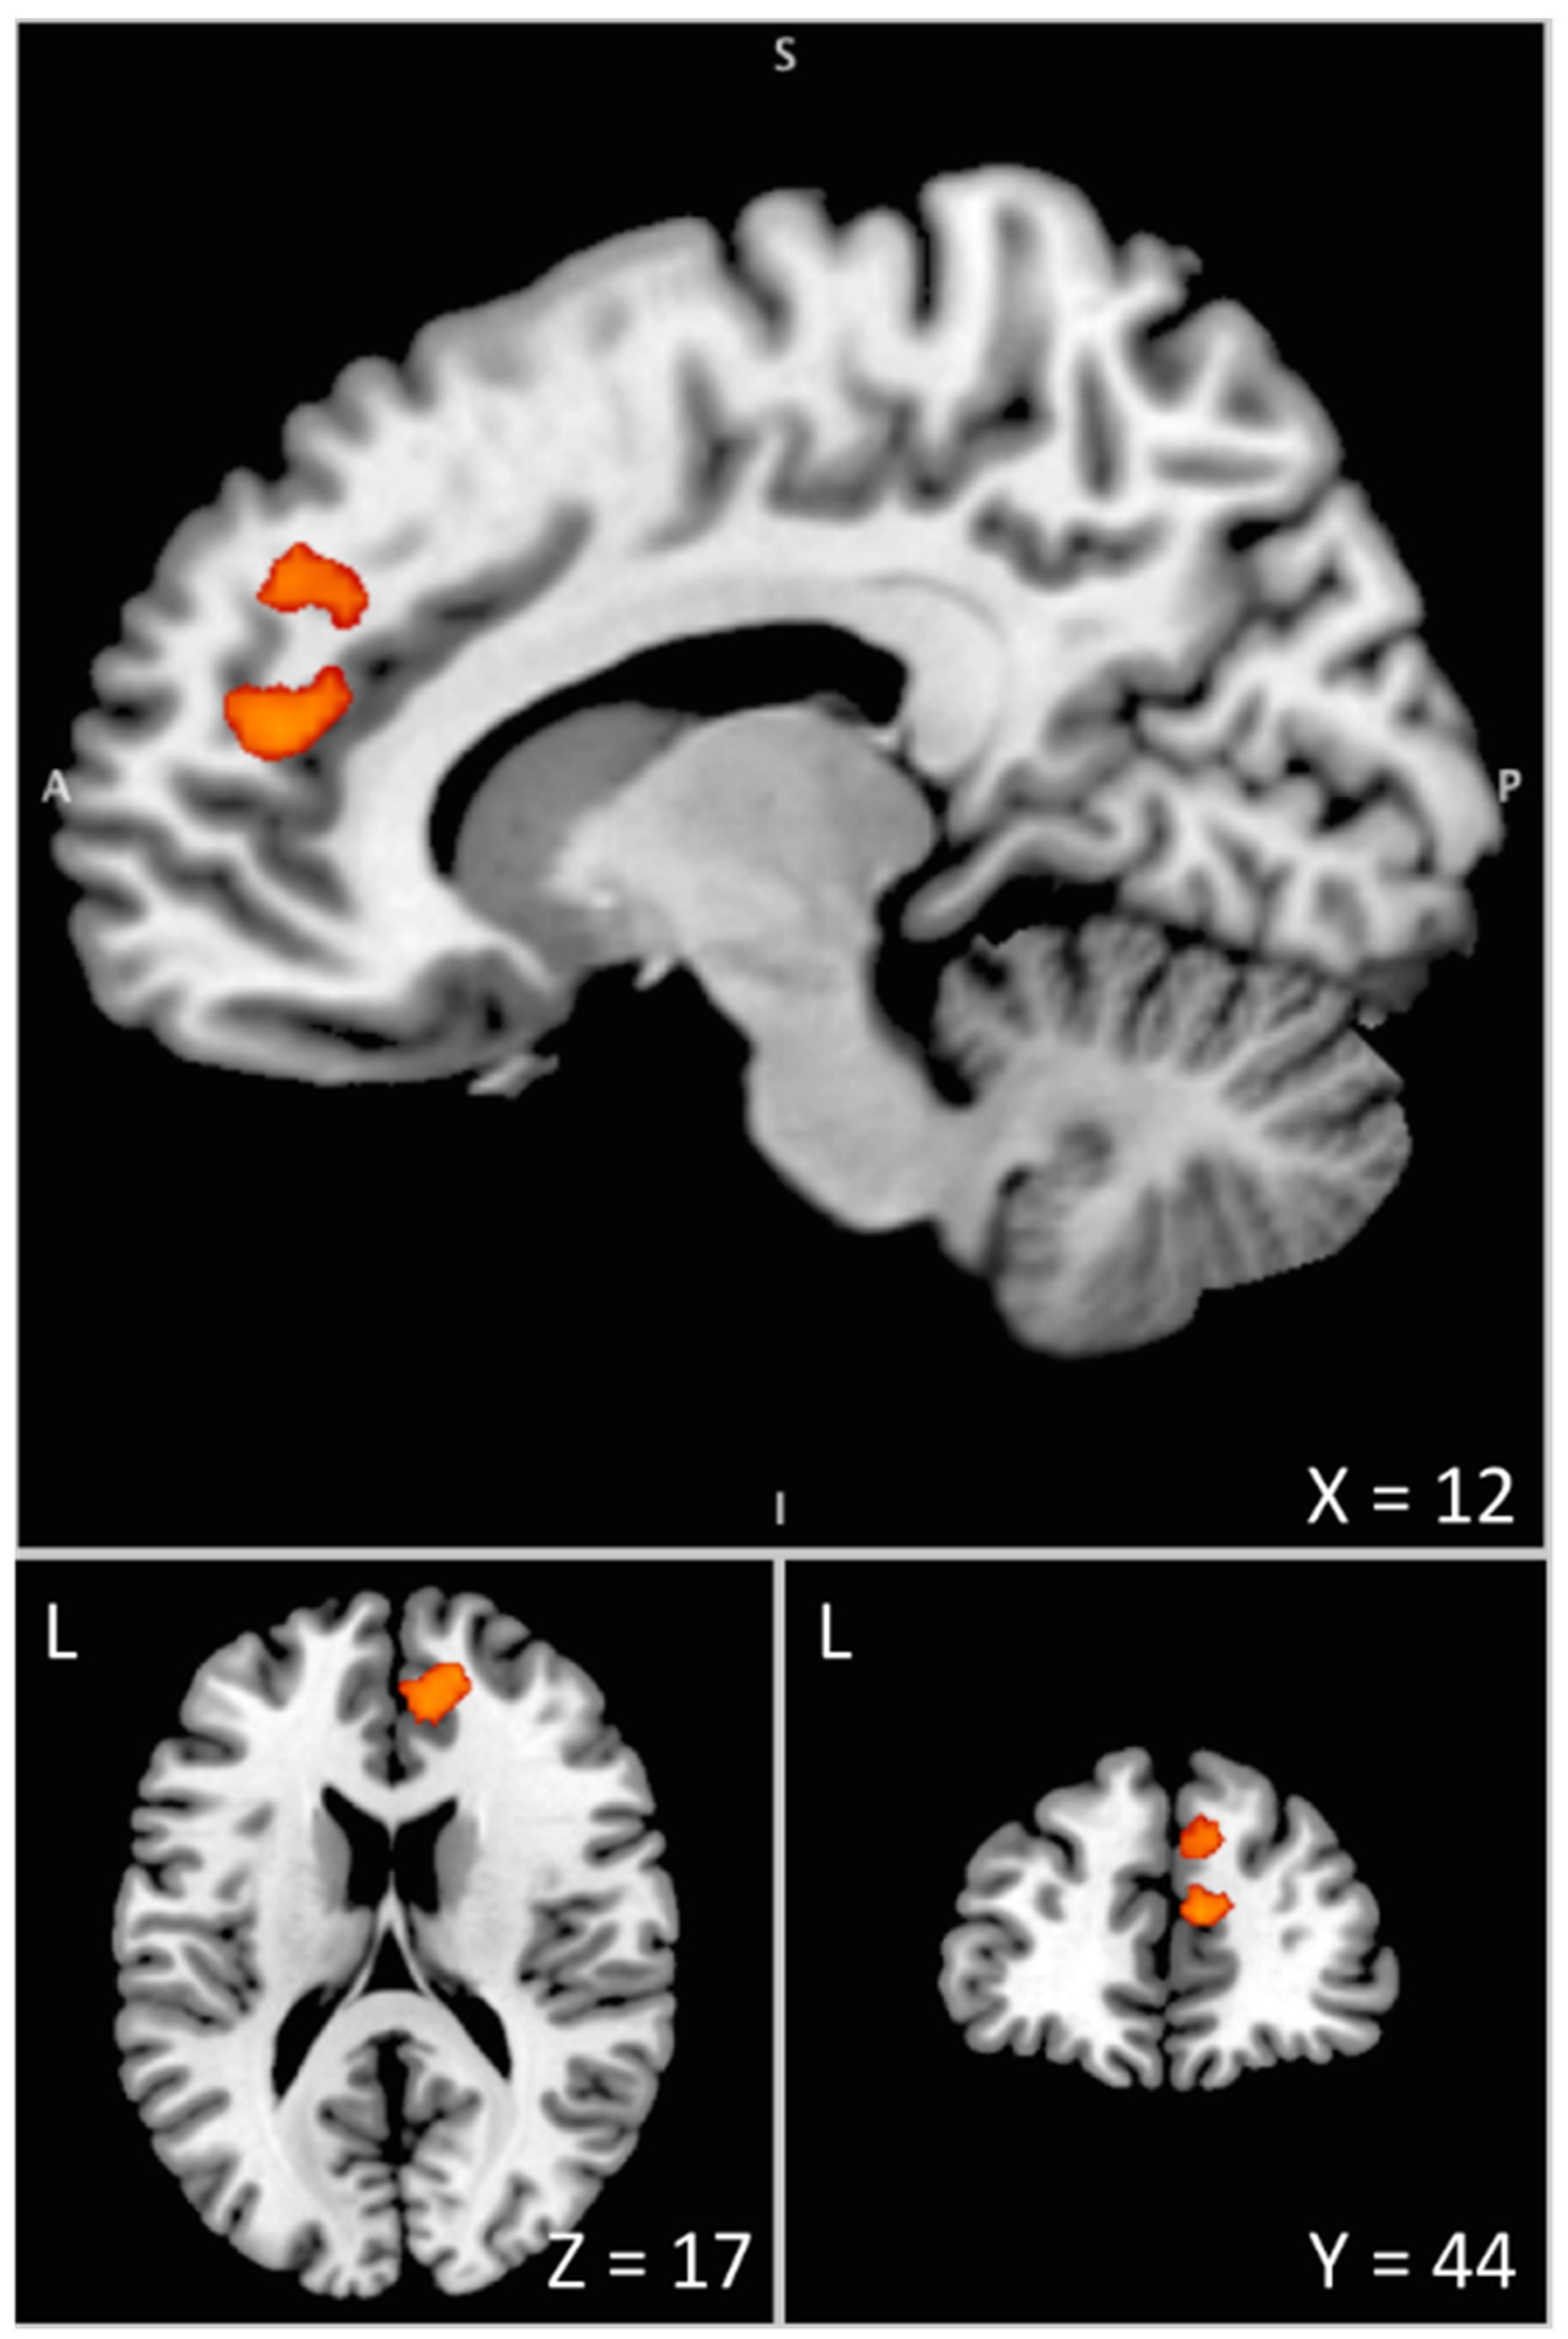

| MNI Coordinates | P Corr | Cluster | ||||||

|---|---|---|---|---|---|---|---|---|

| Areas | BA | Side | x | y | z | Z-Score | Cluster | Size |

| Anterior Cingulate Cortex | 32 | R | 8 | 44 | 16 | 4.21 | 0.037 | 311 |

| Superior Frontal Gyrus | 32 | R | 16 | 50 | 18 | 4.03 | ||

| Superior Medial Frontal Gyrus | 9/32 | R | 10 | 44 | 34 | 3.72 | ||